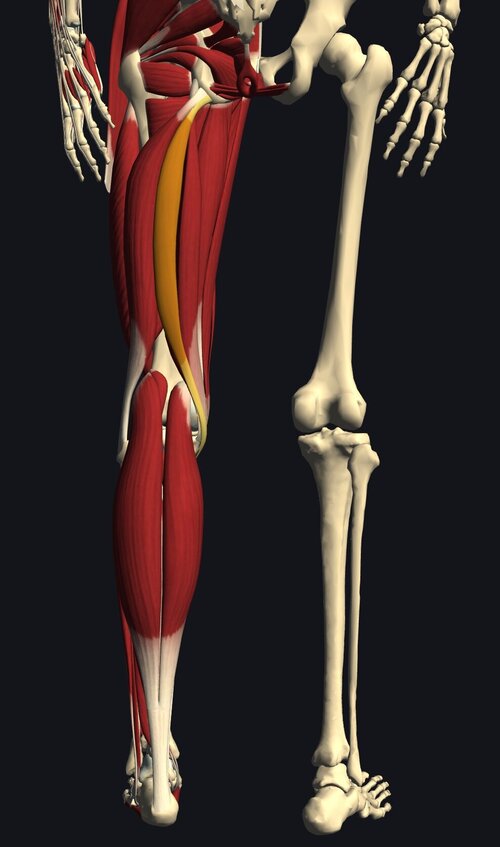

半腱様筋肉離れ.jpeg

しっかり問診、視診、触診後、確認の為にエコー検査。

結果「ハムストリングス 半腱様筋の肉離れ」と判明。

ハムストリングスの肉離れは好発部位の一つで、

症状は断裂部の圧痛と、歩行時等の運動痛が著名、

損傷部位で"ボコッ"と陥凹を触知できる場合もあります。

半腱様筋.jpg